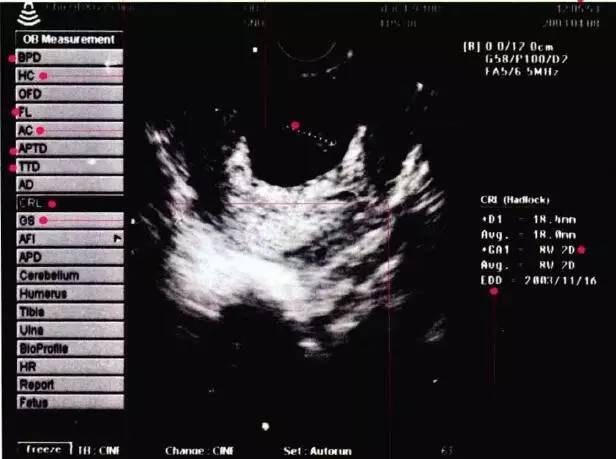

为了好理解,我们看看下面这张B超图像。

(图自 《宝宝圣经》)

左侧从上到下,记一下主要的几个缩写词。多了你们也记不住。

BPD:双顶径,指宝宝头部左右两侧之间最宽部位的长,用来判断胎龄,计算预产期。

HC:头围,确认宝宝成长发育的程度。

FL:股骨长,一般比BPD值小2-3厘米。用FL和BPD可以估计宝宝大小和体重。

AC:腹围。确认胎龄的基准。

AFI:羊水指数,以孕妈的脐部为中心,分上,下,左,右4区域,将4个区域的羊水深度相加,就得到羊水指数,孕晚期羊水指数的正常值是8~18厘米。超过18厘米为羊水增多,少于8厘米为羊水减少。

GP:胎盘分级,一般为0,I,II,III级。

I级为胎盘成熟的早期阶段,回声均匀,一般孕30~32周胎盘为I级。

II缎表示胎盘接近成熟。

III级表示胎盘已经成熟,胎盘内有很多钙化点。越接近足月,胎盘越成熟,回声越不均匀。